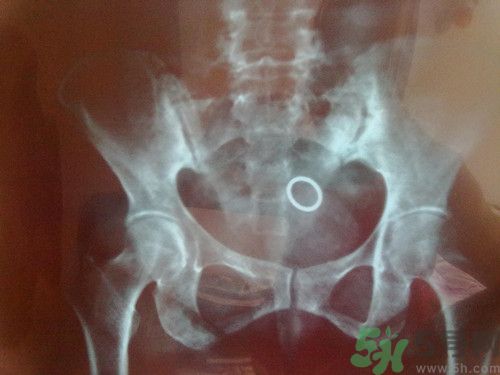

1.強(qiáng)直性脊柱炎。年輕人發(fā)病多,一般不超過(guò)三十歲,男性多于女性。

第一、放射治療:對(duì)脊柱、骶髂關(guān)節(jié)病變進(jìn)行深部X線(xiàn)照射,強(qiáng)直性脊柱炎有效率可達(dá)60%~80%,放射治療可以減輕疼痛,緩解肌肉痙攣,因有種種嚴(yán)重并發(fā)癥,故放射治療目前很少采用,一般只限于各種常規(guī)治療都無(wú)效的特殊病例。即使在這些病例中,總的放射劑量也不應(yīng)超過(guò)1500拉德。